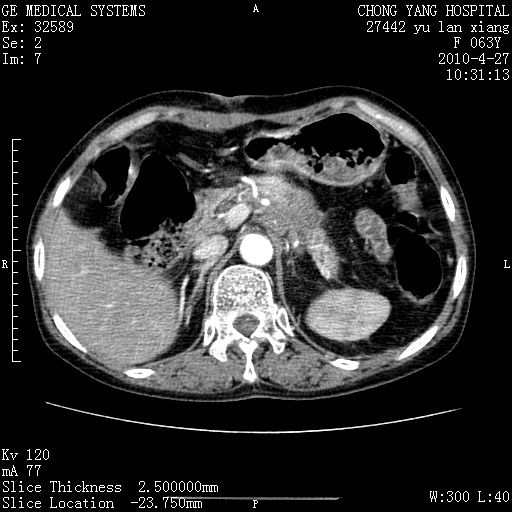

标题: CT26066:F63Y 上腹正中压痛半月,CA199:7400u/ml,MR示胰腺炎伴 [打印本页]

胰腺癌侵犯腹腔动脉干-分支、胃壁、左侧膈肌伴胰周及腹膜后淋巴结转移、胆囊切除术后。

胰腺癌侵犯腹腔动脉干-分支、胃壁、左侧膈肌伴胰周及腹膜后淋巴结转移、胆囊未显影。